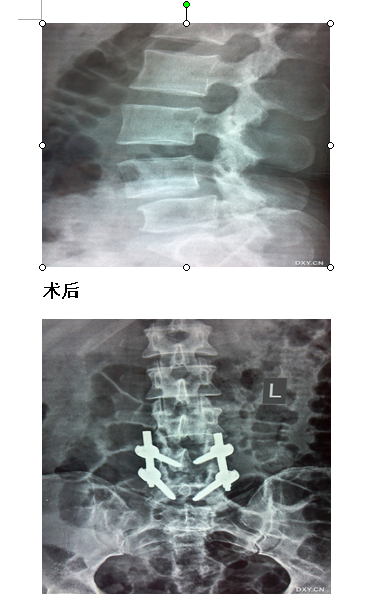

脊柱组:主要针对颈椎病,颈椎管狭窄症;腰椎间盘突出症,腰椎管狭窄症,腰椎滑脱症及其它类型的脊柱退变;新鲜及陈旧性脊柱脊髓损伤;颈胸腰椎结核;各种原因颈胸腰椎畸形等疾病的诊疗;开展颈椎病前后路的手术治疗;腰椎间盘脱出症、脊柱各类创伤、脊柱滑脱等手术治疗。